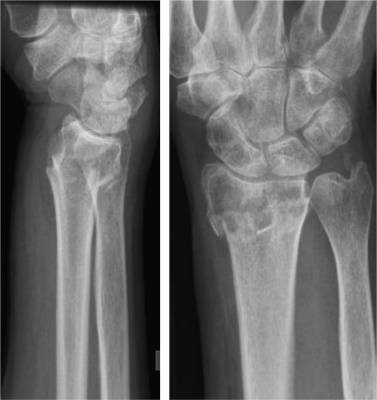

Fracturas del radio distal en la población anciana

No encontramos evidencia clara de la superioridad clínica de la cirugía de fractura de radio distal entre los adultos mayores al año; sin embargo, el tratamiento quirúrgico puede producir una recuperación más rápida al nivel previo de actividad en los pacientes ancianos.

Operaciones secundarias y extracción de implantes, mientras que en el tratamiento no quirúrgico puede producirse una pérdida de alineación sintomática y una unión defectuosa. En pacientes de edad avanzada, el tratamiento no quirúrgico puede considerarse el estándar de oro.